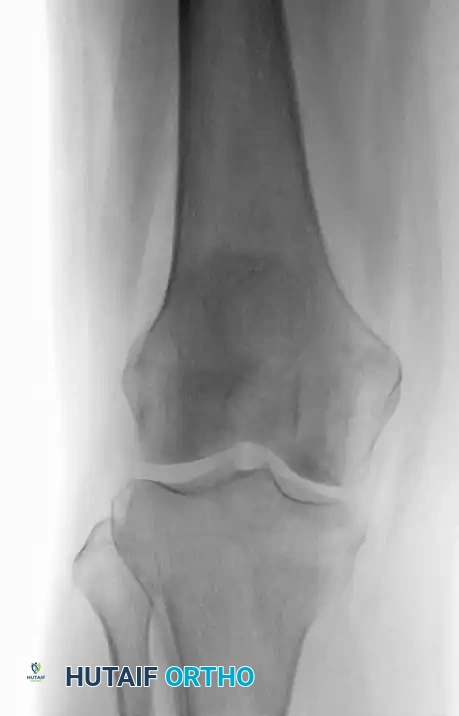

Fig. 20-22: (A and B) Pathological fracture of the right proximal tibia occurring through a large, expansile “brown tumor” of hyperparathyroidism in a 55-year-old woman.